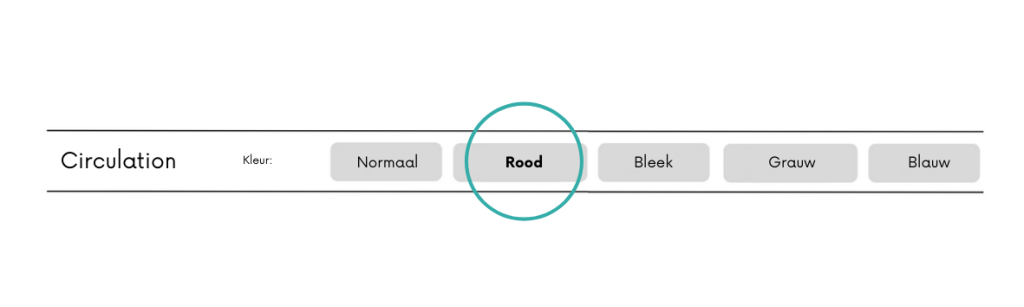

Tijdens triage is het belangrijk om te weten of de kleur van de huid veranderd is.

- Is er iets veranderd aan de kleur van het gelaat?

- Is de kleur van het gezicht anders dan normaal?

Denk na over de vraagstelling. Wat is uw huidskleur is geen gepaste vraag. Dit kan als racistisch worden opgevat! Het gaat erom of de huid anders eruit ziet dan normaal. En zo ja, vraag het volledige toestandsbeeld uit om te kunnen bepalen of het een circulair probleem is.

Is de kleur van de huid niet veranderd scoor je op normaal. Rood valt ook nog onder normaal. Wanneer iemand bleek ziet is het belangrijk om na te denken over de oorzaak van het bleek zien. Iemand die ziek is ziet veelal bleek. Is iemand bleek na een trauma denk dat na over inwendige en uitwendige bloedingen. Is er veel bloed verloren uitwendig? Denk dat na of er ook inwendig letsel kan zijn!

Iemand die grauw of blauw ziet kan een groot circulair probleem hebben, er is te weinig zuurstofrijk bloed wat circuleert. Vraag direct door. Is er sprake van bijvoorbeeld pijn op de borst? Erge hoofdpijn? Een trauma? Is de patiënt duizelig? Is de patiënt misselijk? Is de patiënt aan het zweten?